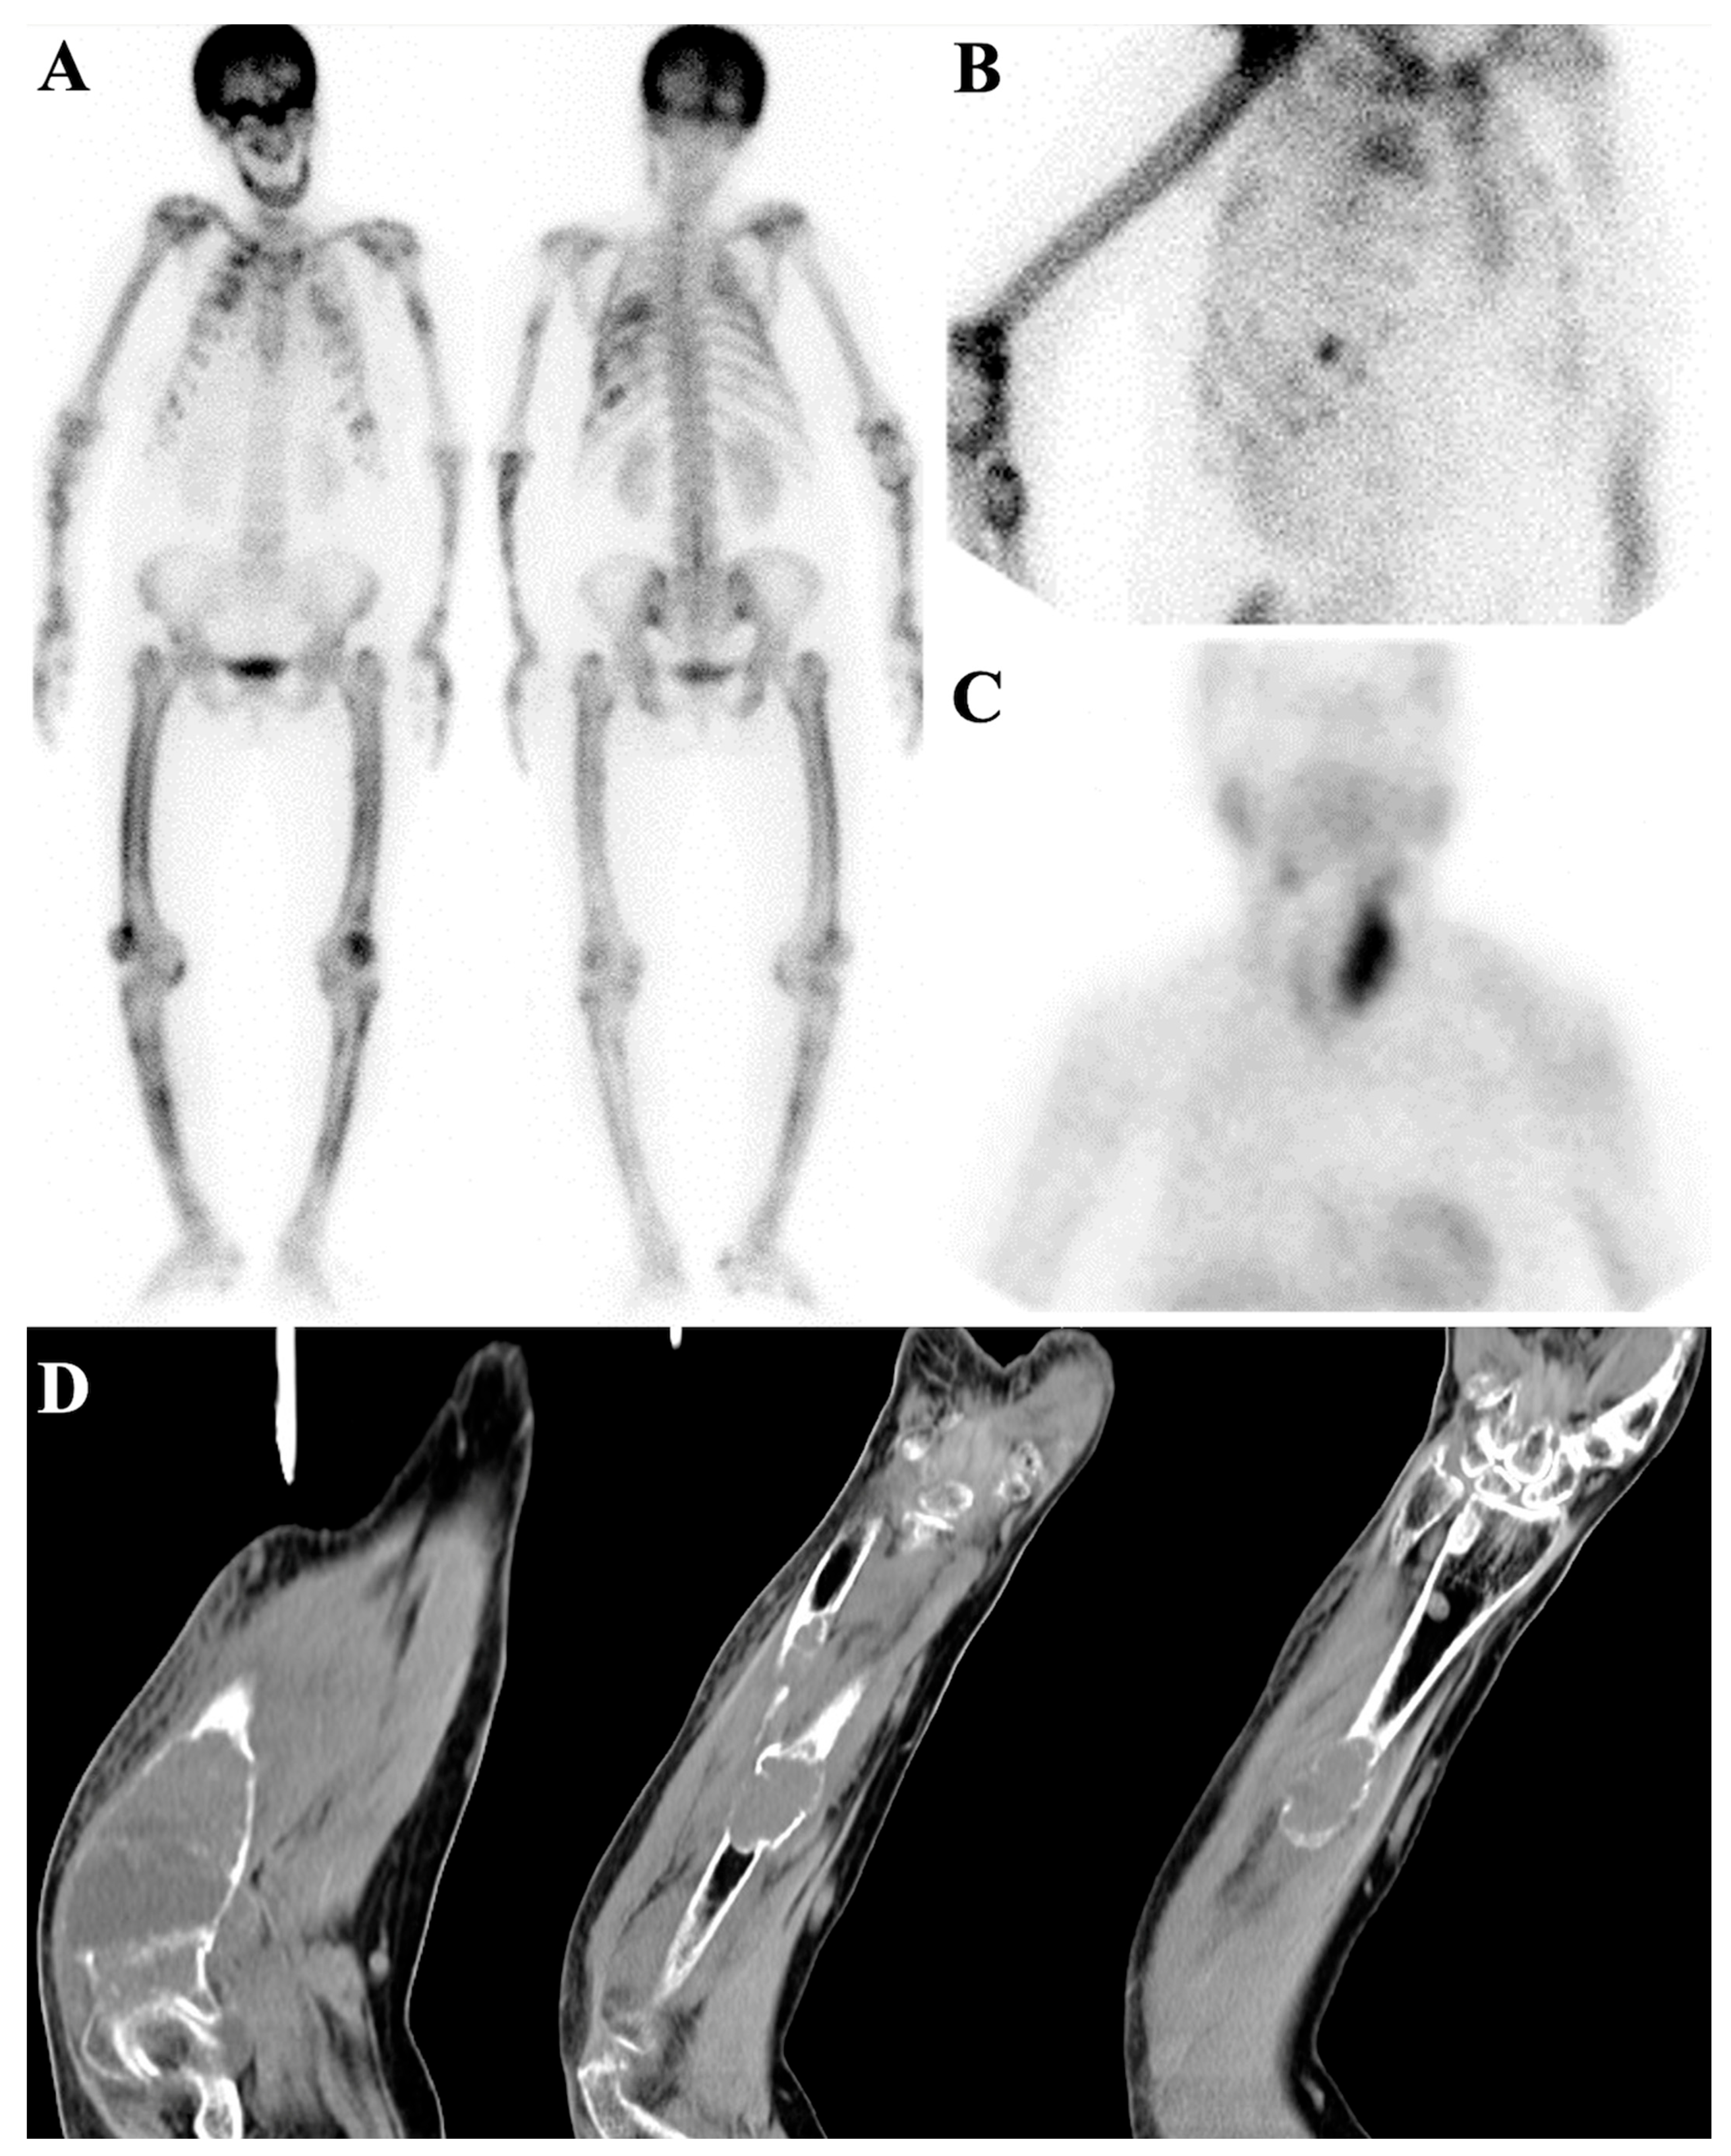

7.1.1. Superscan Pattern in Patients with Prostate Cancer

7.1.2. Dynamic Changes in Prostate Cancer Patients with Superscan